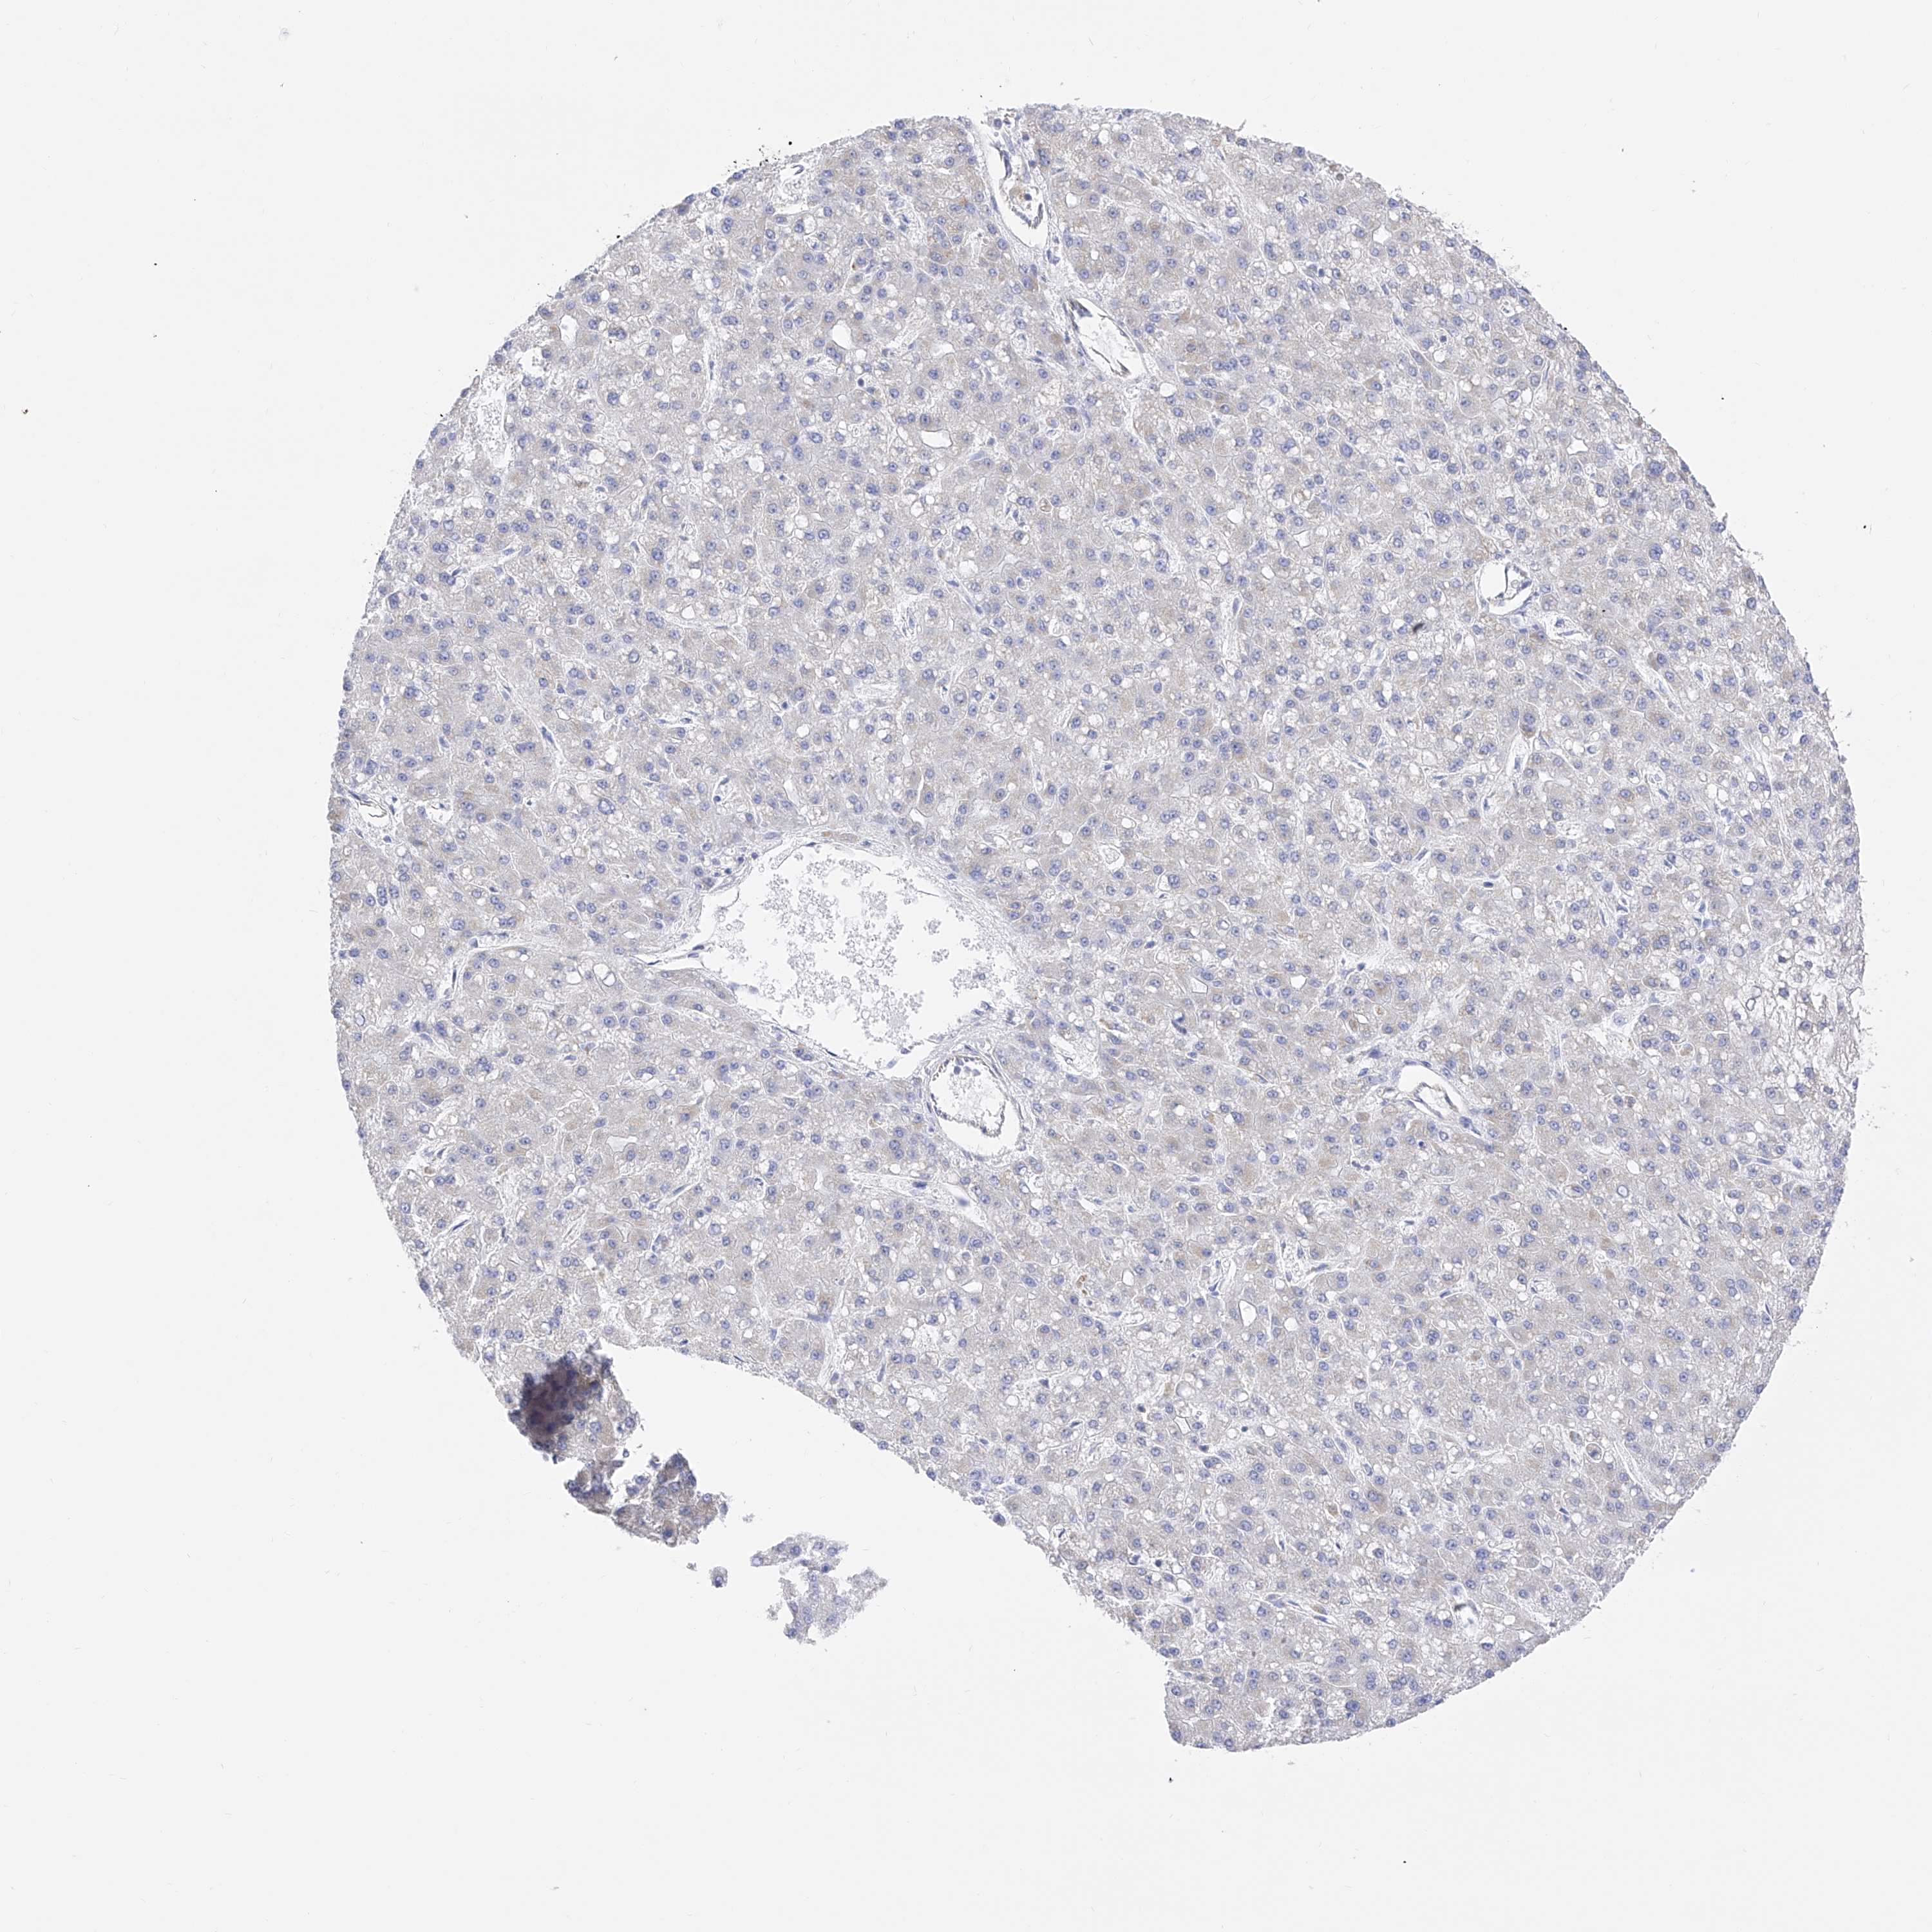

LIVER CANCER - Protein expressioni

A mouse-over function shows sample information and annotation data. Click on an image to view it in a full screen mode. Samples can be filtered based on level of antibody staining by selecting one or several of the following categories: high, medium, low and not detected. The assay and annotation is described here.

Note that samples used for immunohistochemistry by the Human Protein Atlas do not correspond to samples in the TCGA dataset.

Antibody stainingi

Antibody staining in the annotated cell types in the current human tissue is reported as not detected, low, medium, or high, based on conventional immunohistochemistry profiling in selected tissues. This score is based on the combination of the staining intensity and fraction of stained cells.

Each image is clickable and will lead to virtual microscopy that enables deeper exploration of all samples and also displays staining intensity scores, fraction scores and subcellular localization as well as patient and tissue information for each sample.

Antibody HPA030188

Antibody HPA030189

Antibody CAB002210

Cholangiocarcinoma

Carcinoma, Hepatocellular, NOS